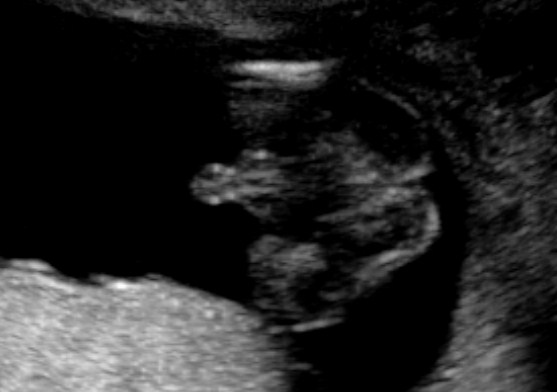

Tech said boy! Think so?

Can you ladies help please? This is my 20 weeks scan. Tech said it's 90% boy as she can see penis. Do you ladies think so? She did not point out the parts to me. And when I look at these pics, I think it's the boy bits I am looking at, but I am not too sure???